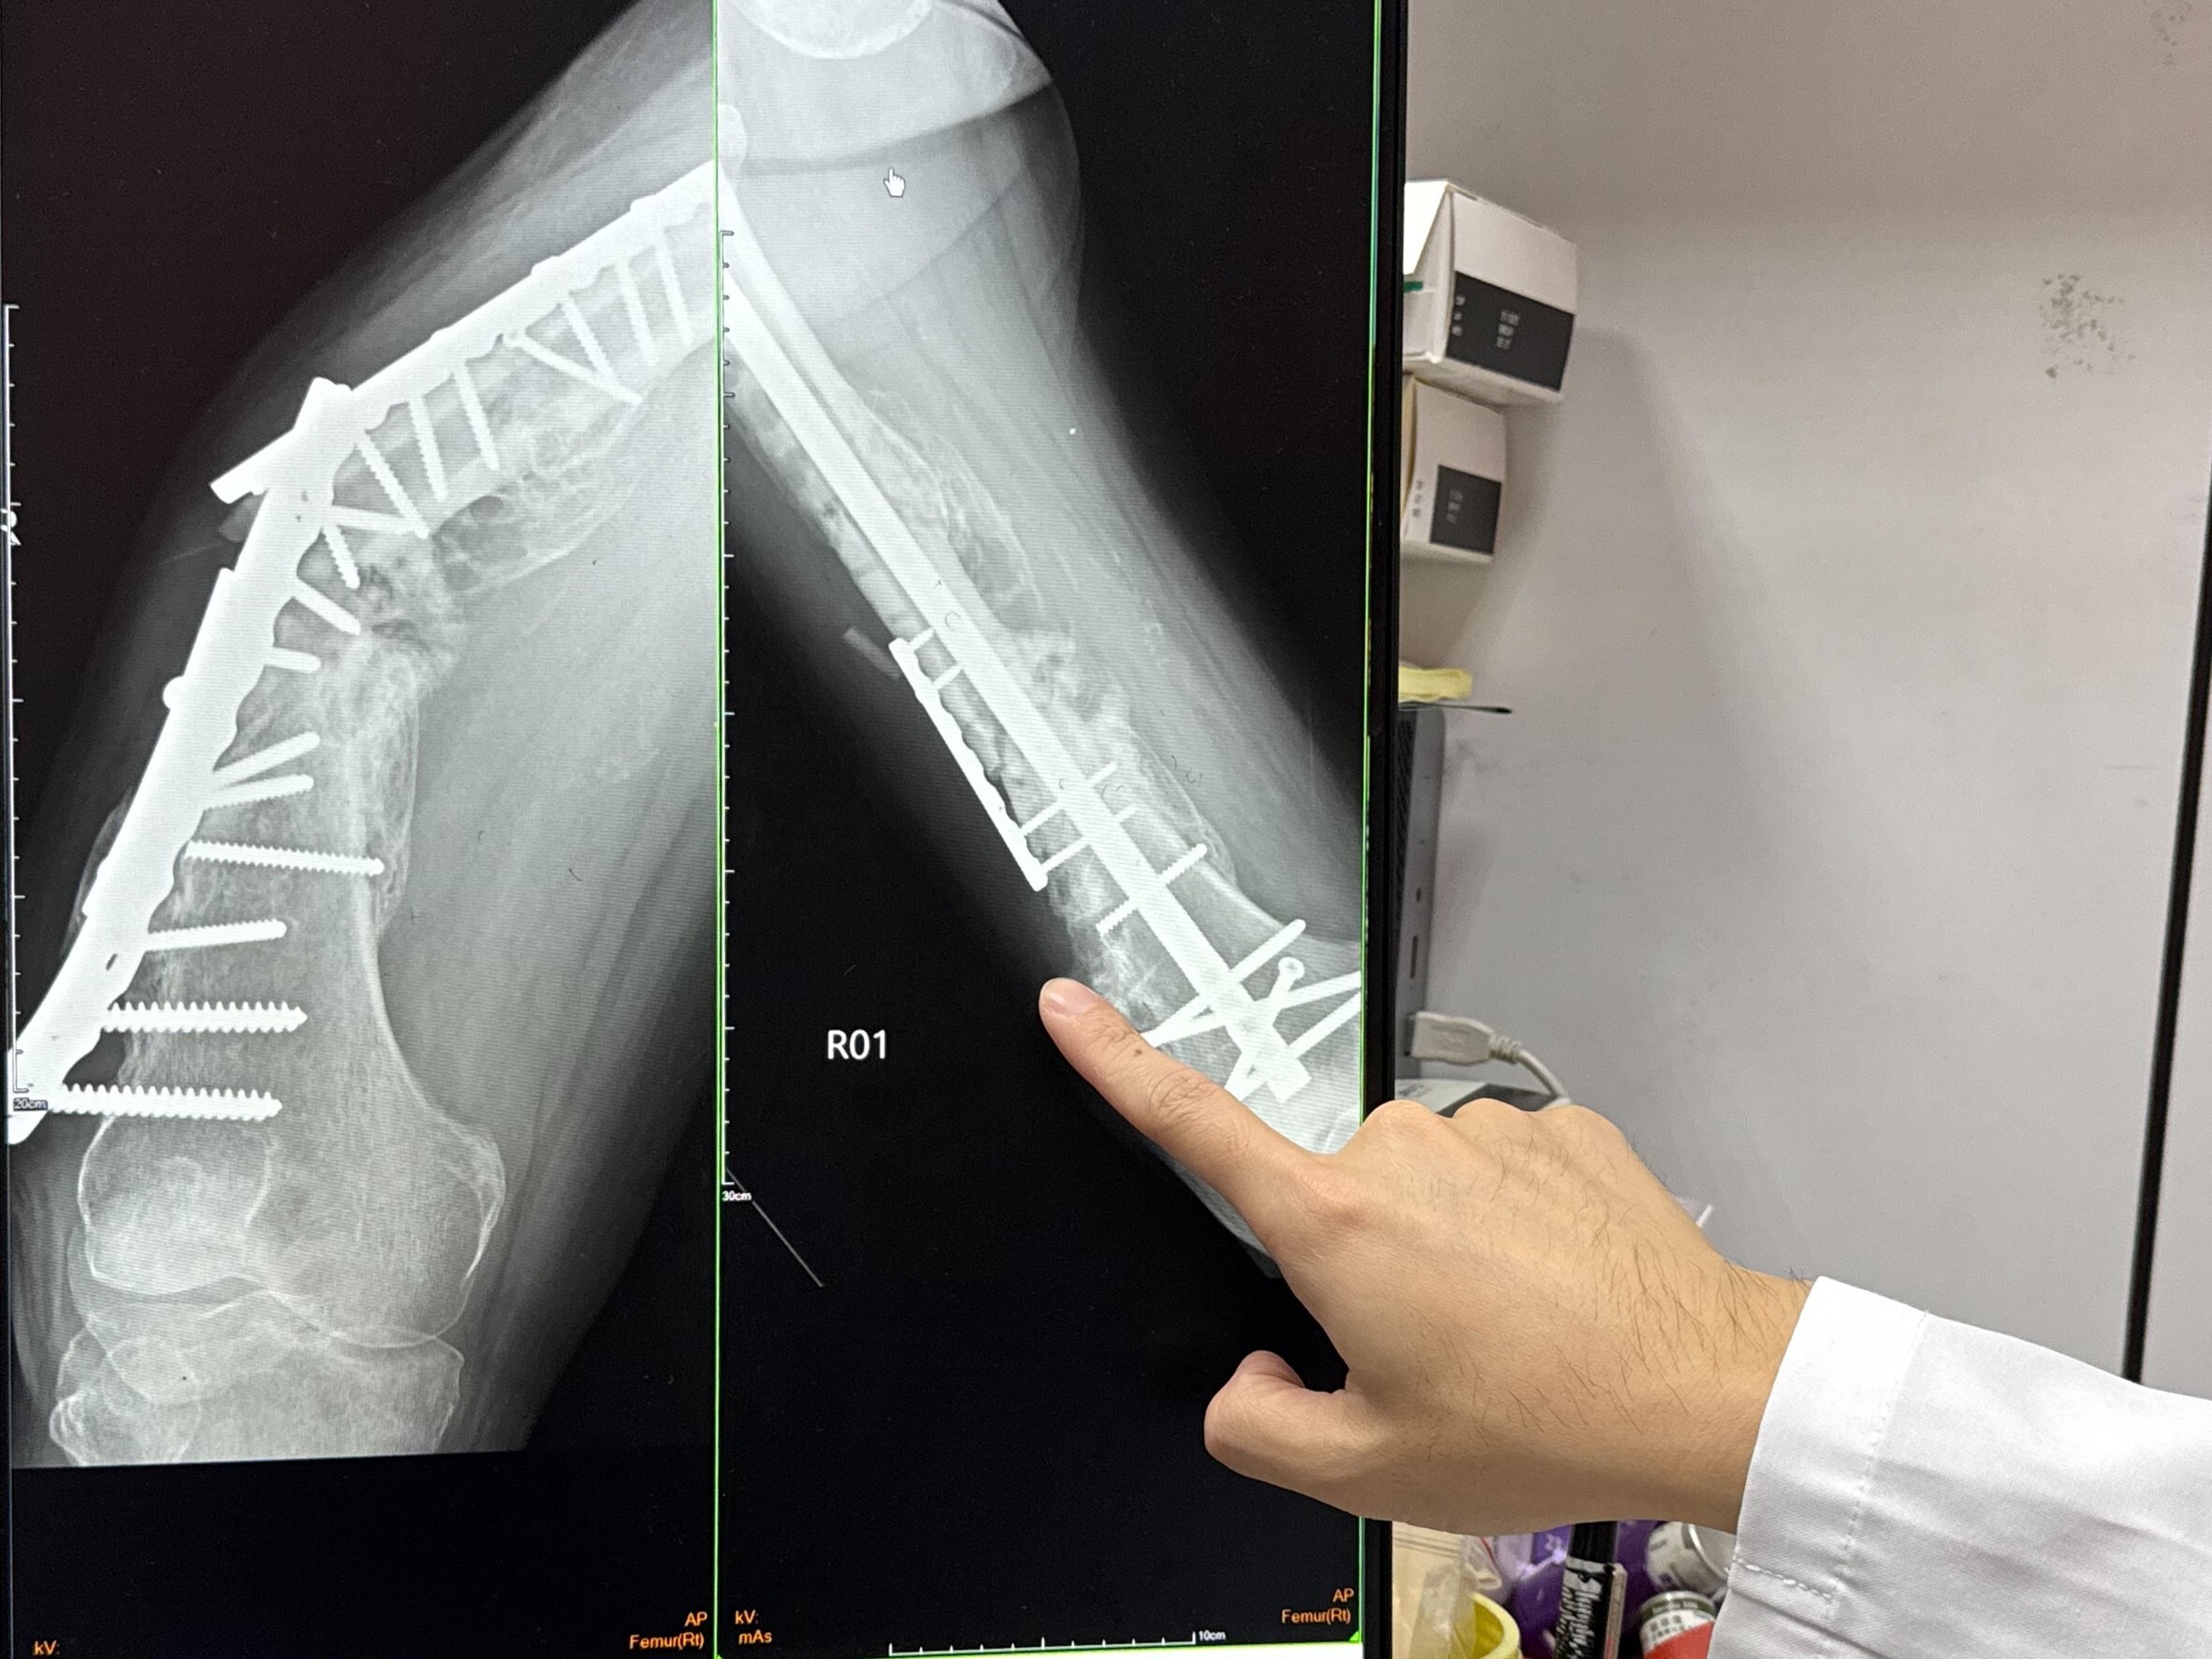

▲ 8旬翁大腿斷三截因鋼板金屬疲勞斷裂(左),再用髓內鋼釘(右)固定。(圖/李綜合醫療社團)

在經過詳細評估後,廖醫師決定為王老翁進行第二次手術。手術中,醫師將壞死的骨頭移除,並拆除舊有的鋼板和鋼釘,改用髓內鋼釘固定,讓骨頭有機會再次癒合。術後,王老翁能夠立刻下床負重,恢復日常行走功能。經過一個多月的復健,他已經能夠站立行走,並表示要努力復健,期待明年再度參加大甲媽祖遶境。